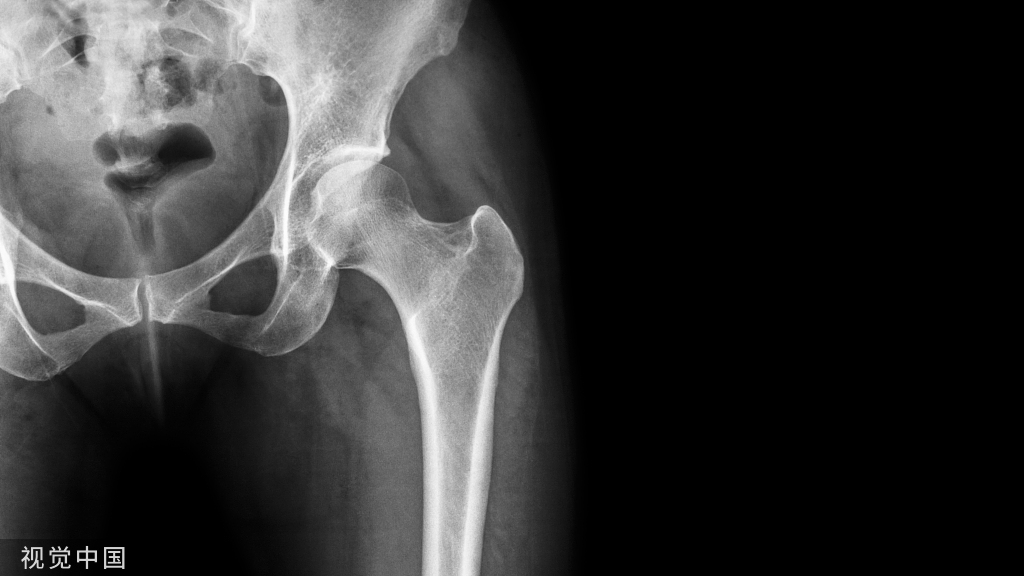

肩关节脱位

肩关节脱位(shoulder dislocation):很常见,约占全身关节脱位的50%。多发生在青壮年、男性较多。按肱骨头脱位的方向分为前脱位和后脱位等。肩关节前脱位者很多见,常因间接暴力所致。

肩关节前脱位(Anterior shoulder dislocation):肩关节脱位按肱骨头的位置分为前脱位和后脱位。肩关节前脱位者很多见,常因间接暴力所致,如跌倒时上肢外展外旋,暴力经过肱骨传导到肩关节,使肱骨头突破关节囊而发生脱位。

由于暴力的大小、力作用的方向以及肌肉的牵拉,前脱位时,肱骨头可能位于锁骨下、喙突下、肩前方及关节盂下。